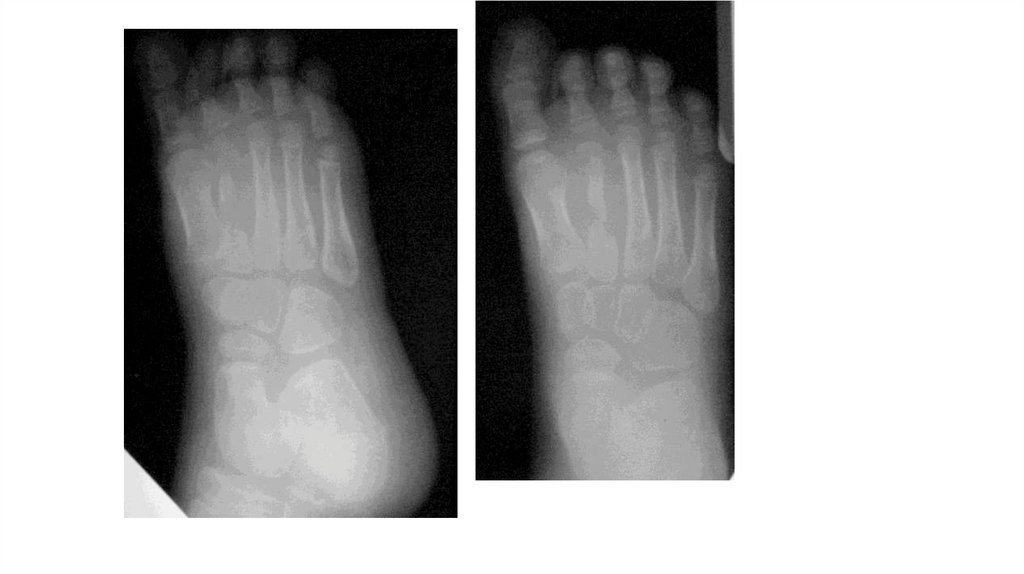

«Воспалительные

заболевания опорнодвигательного аппарата»